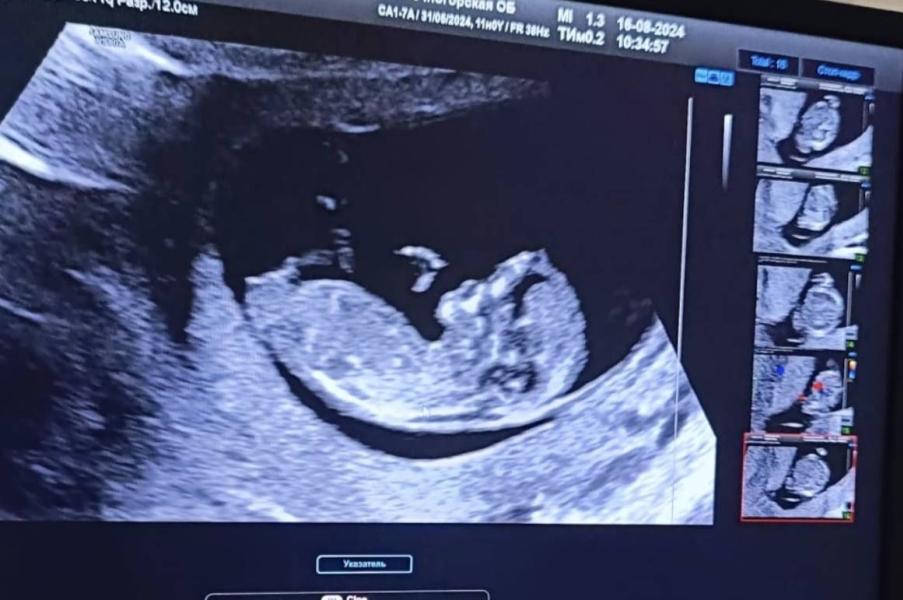

Первое УЗИ стало скриннингом, срок оказался на неделю больше. Ну об этом у меня были подозрения, что овуляция была ранняя. После двух замерших, я усердно наблюдала за выражением лица врача, монитор не видно было. Лицо было напряжённое, а потом врач сказала: малыш на 12 недель, не 11. Значит, будет скриннинг.